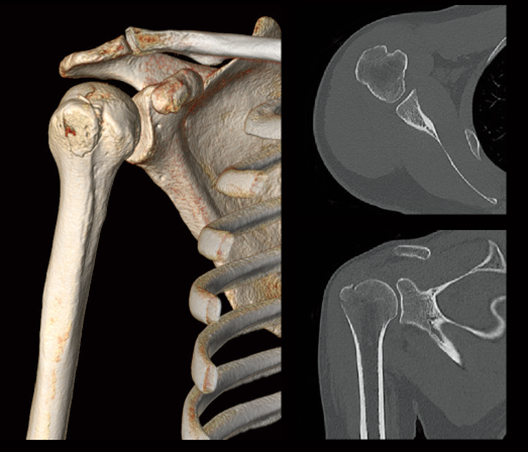

Humeral greater tuberosity fracture

- * Images other than the axial image were processed by the 3D image analysis system SYNAPSE 3D.